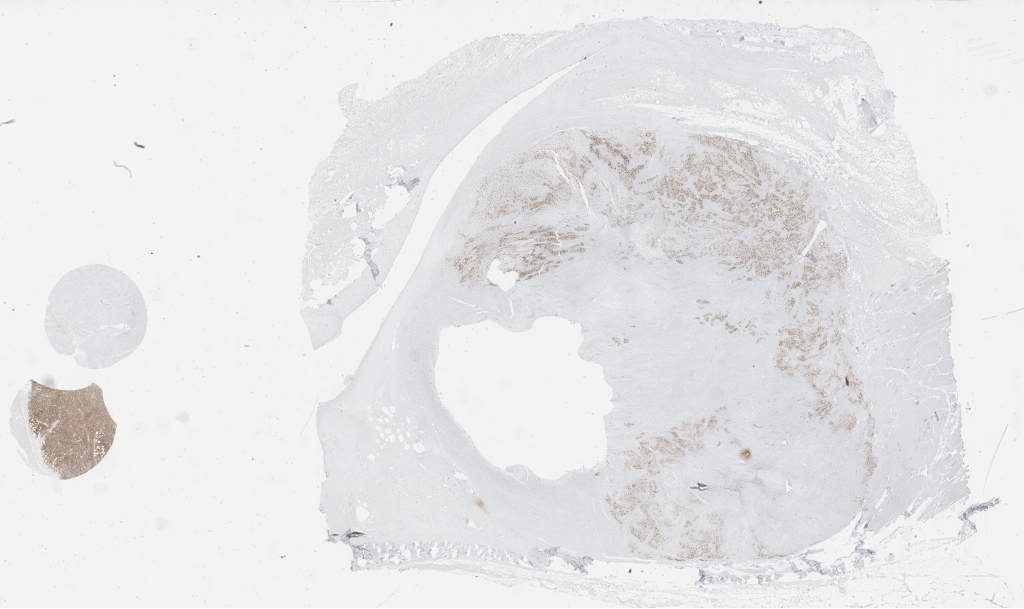

myogenin.svs

125495

x

74526

@

40X